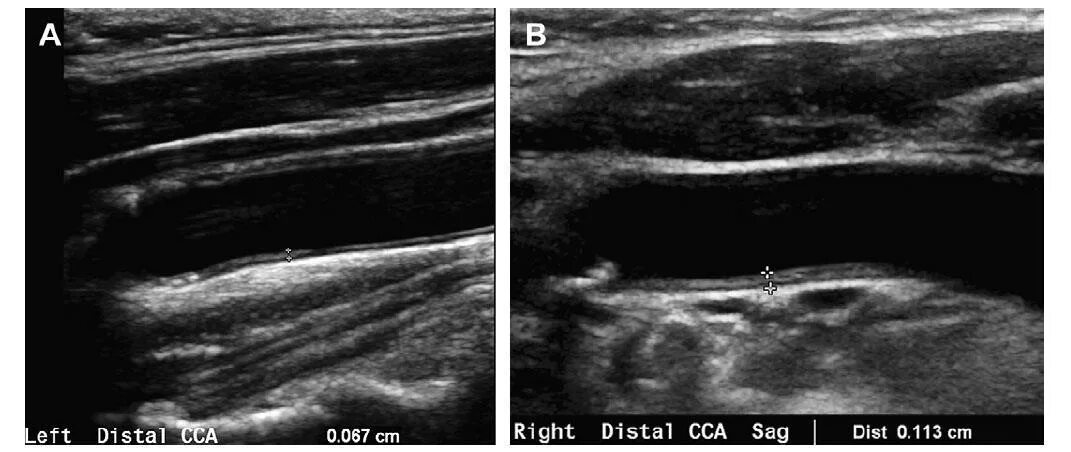

Атеросклеротическая бляшка узи